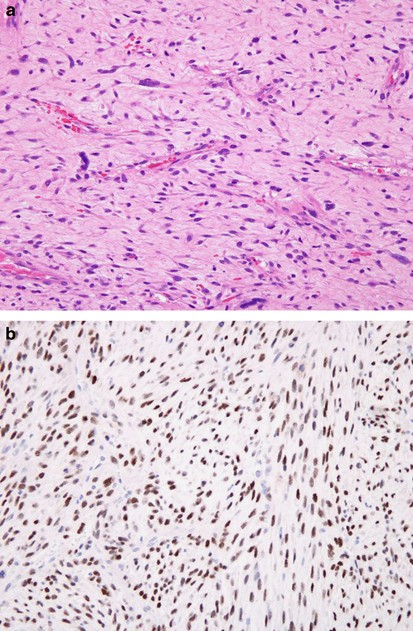

The results are summarized in Table 1. Overall, TLE1 was expressed by 18 of 20 (90%) of synovial sarcoma, with 17 cases (85%) showing 2–3+ positivity (Figures 1, 2 and 3). However, TLE1 expression was also seen in 53 of 143 (37%) non-synovial sarcoma, with 36 such cases (25%) showing 2–3+ positivity. TLE1 expression was commonly seen in peripheral nerve sheath tumors, including 30% of malignant peripheral nerve sheath tumors (Figures 4 and 5), 100% of schwannomas (Figure 6) and 33% of neurofibromas. Figures 7 and 8 illustrate TLE1 expression in other non-synovial sarcomas (alveolar rhabdomyosarcoma and myxoid liposarcoma). In TLE1-positive non-synovial sarcomas expression was often heterogenous, with some fields showing near uniform positivity, and others showing only patchy or even absent positivity. The overall sensitivity and specificity of TLE1 expression for the diagnosis of synovial sarcoma was 85 and 75%, respectively. Among non-neoplastic tissues, nuclear TLE1 expression was occasionally present in basal keratinocytes, adipocytes, perineurial cells, endothelial cells and mesothelial cells.